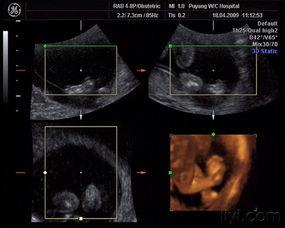

4. 定期产检:按时进行产检,了解胎儿的发育情况。

四、怀孕三个月:真实图片分享

下面,让我们一起欣赏一组怀孕三个月的真实图片,感受一下这个特殊时期的美丽变化。